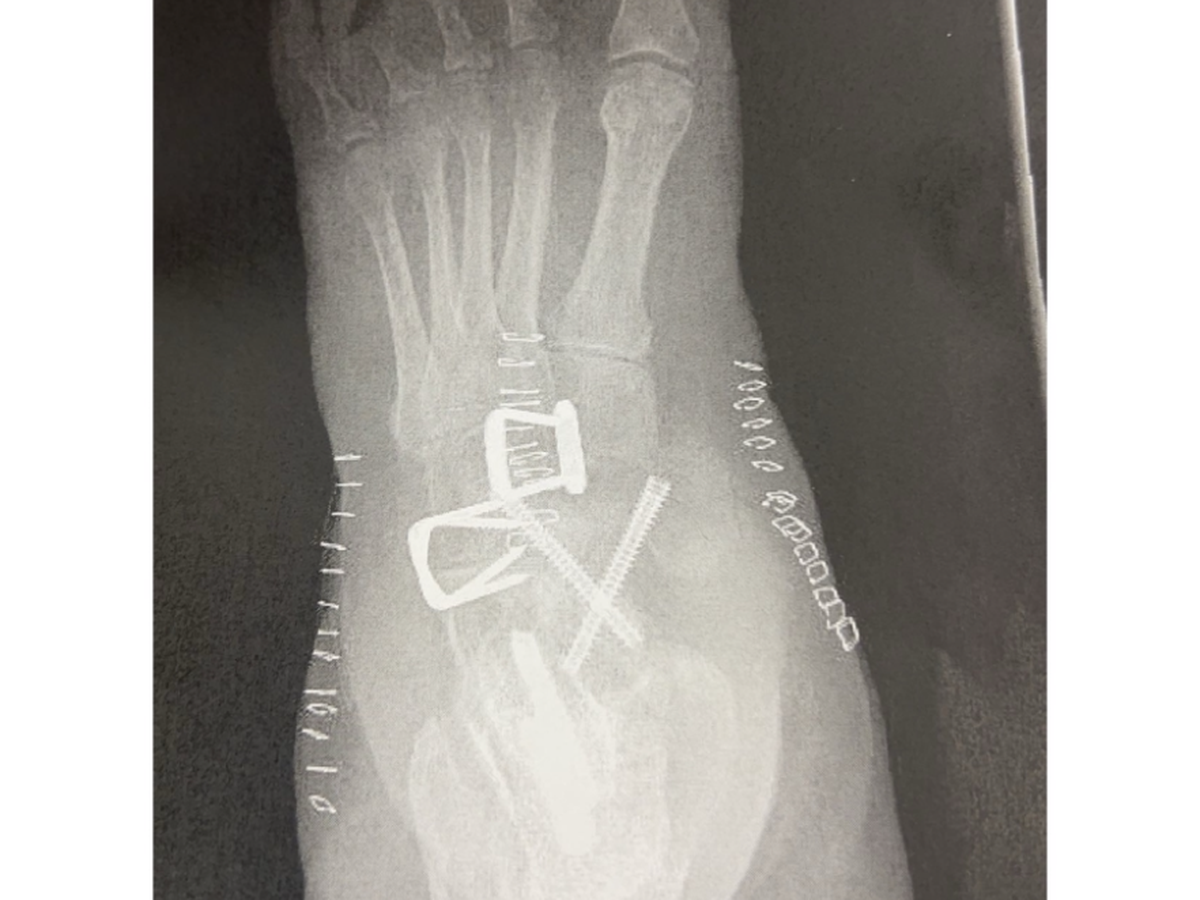

I'm employed full time but I'm not in a position to afford the remaining balance of my surgery that the insurance did not cover. As you are aware I’ve been out of work for 6 weeks now and my income is $170/week from short term disability. The doctor has mentioned that I may be out another 2 weeks or longer. I still cannot walk ; using a walker and knee scooter for doctor visits. Still bed ridden. I’m not allowed to put weight on the foot.